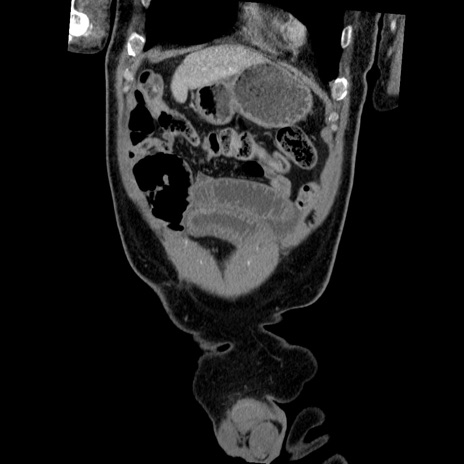

横断像

【症例】50歳代男性

【主訴】腹痛

【現病歴】AVMからの被殻出血のため回復期リハ病棟入院中。 本日午後3時頃急に下腹部痛が出現した。

【既往歴】AVM、被殻出血、虫垂炎、高血圧

【身体所見】意識晴明、左半身不全麻痺、会話の理解は良好、36.5°C、腹部:膨隆、全体に板状硬、下腹部正中に圧痛点あり、反跳痛-、筋性防御不明、右下腹部にope scar

【データ】WBC 9400、CRP 0.06